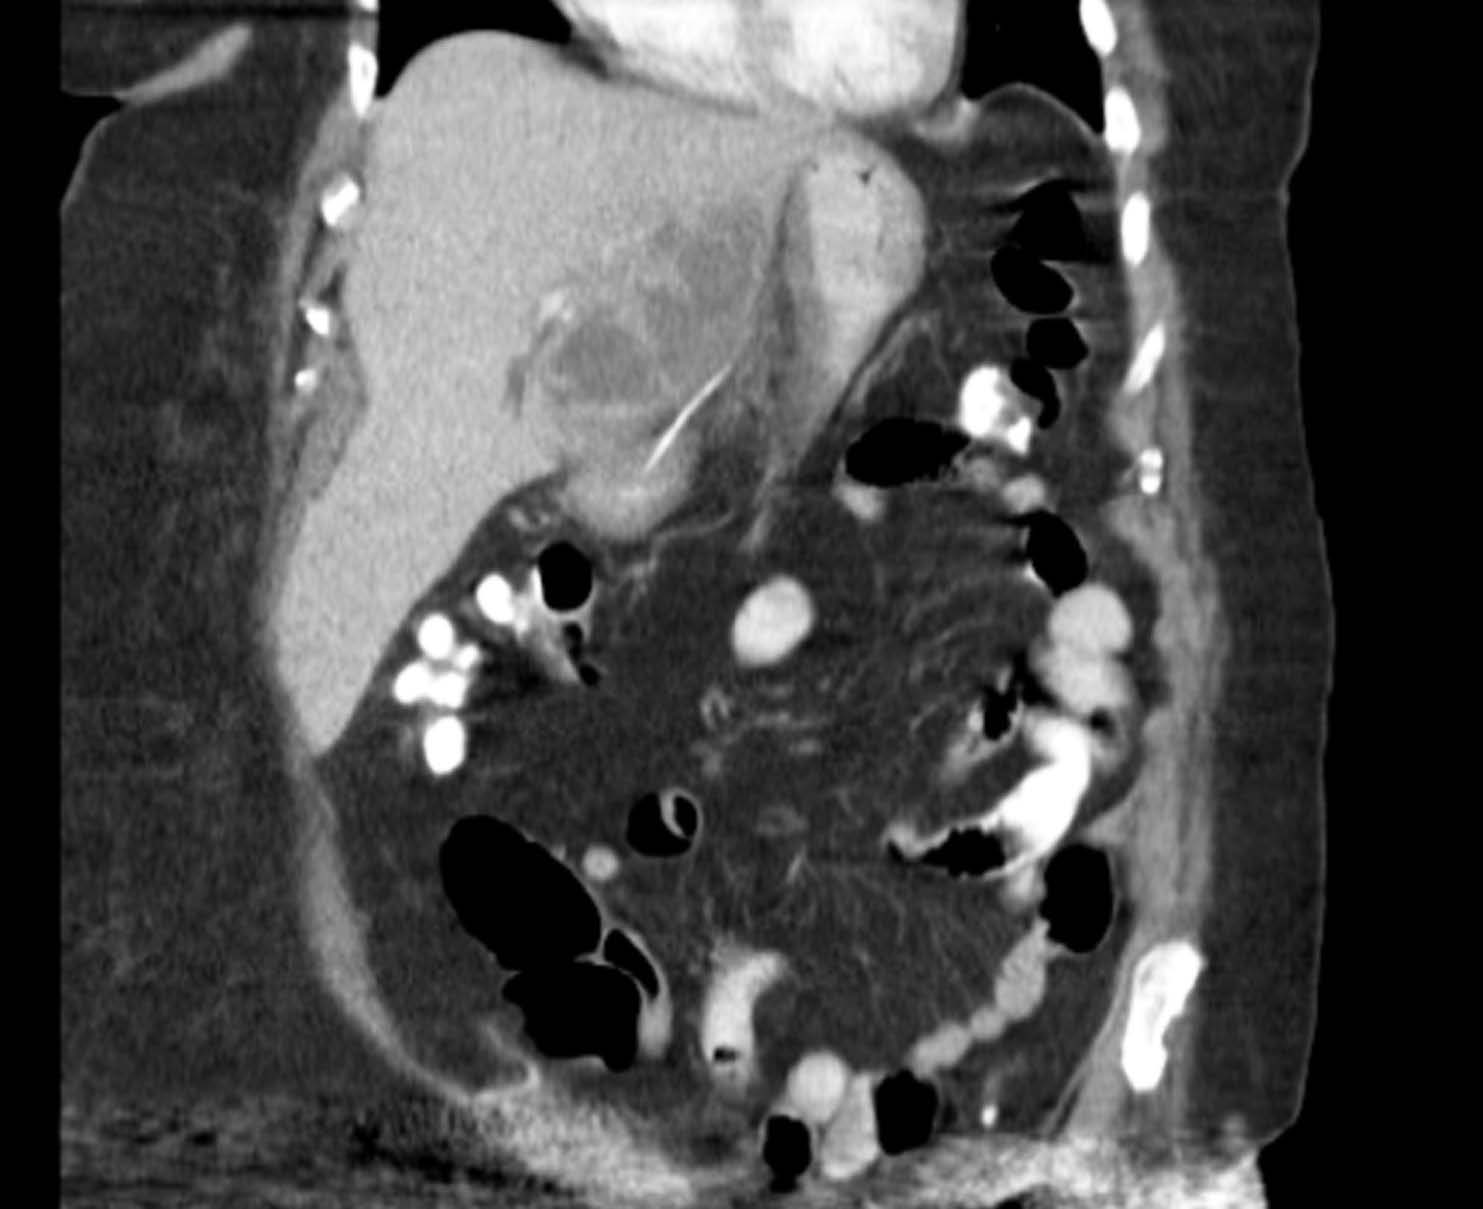

Initial abdominal CT scan demonstrating hepatic abscess. Download Scientific Diagram Liver Abscess X Ray pyogenic liver abscesses usually develops in the context of biliary disease, portal pyemia of various causes,. Amoebic hepatic abscesses can sometimes be difficult to differentiate from other liver abscesses. liver abscess is a localized infection in the liver parenchyma that may be bacterial, fungal, or parasitic in origin. They tend to be round or. imaging tests are. Liver Abscess X Ray.